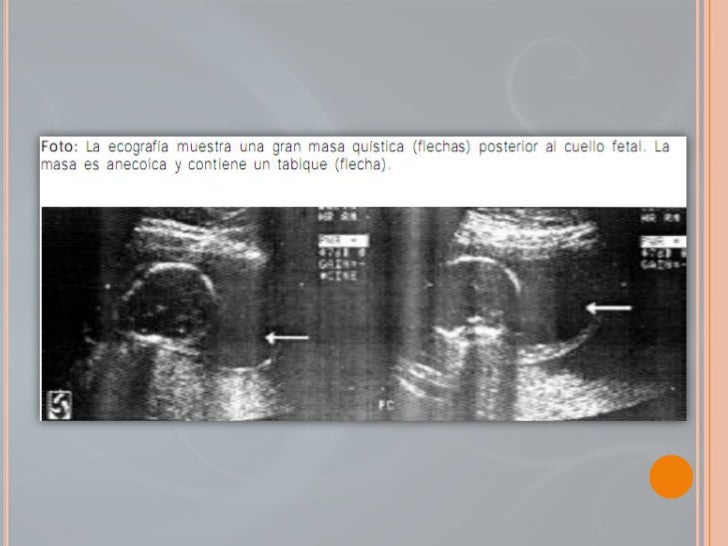

Las malformaciones linfáticas pueden detectarse en el feto humano mediante ecografía si son de tamaño suficiente. La detección de una malformación quística puede dar lugar a más investigaciones, como la amniocentesis, para evaluar si existen anomalías genéticas en el feto. Las malformaciones linfáticas pueden descubrirse después del nacimiento o en niños mayores/adultos, y suelen presentarse como una masa o como un hallazgo incidental durante la obtención de imágenes médicas.

La verificación del diagnóstico puede requerir más pruebas, ya que en los niños pueden aparecer múltiples masas quísticas.[9] El diagnóstico por imagen, como la ecografía o la resonancia magnética, puede proporcionar más información sobre el tamaño y la extensión de la lesión.